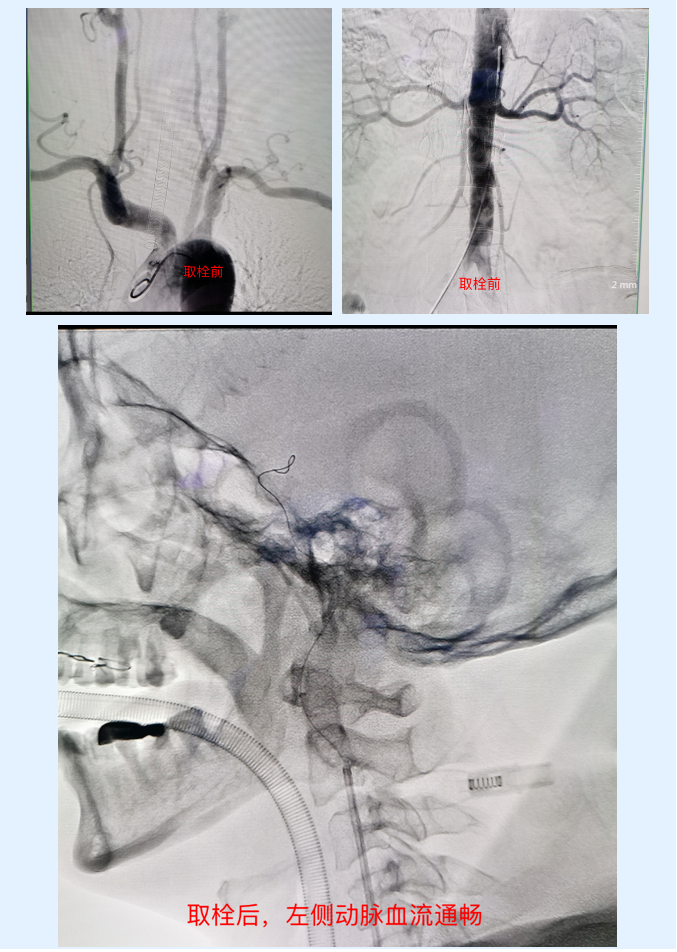

近日,患者陈某有高血压病史10余年,一直未规律服药,8.5小时前饮酒后,家属发现患者右侧肢体活动不灵,对于别人说话也不能完全听不懂,就连自己的名字都无法答出,紧急情况下,家属拨打120送至长安区医院急诊科。急诊科医务人员接到患者后,立即通知神经内科医生,迅速启动卒中绿色通道,神经内科副主任郝宪军充分评估患者后,结合患者头颅ct结果确定患者为脑卒中——左侧颈内动脉闭塞。但患者发病来院已经错过溶栓时间窗,当时唯一的办法就是介入取栓,患者出现大血管闭塞,若不及时进行介入取栓,随着时间推移,脑组织会因动脉缺血而导致大面积坏死,重者将会造成偏瘫,甚至会危及生命!在征得患者及家属同意后,郝宪军医师紧急联系介入手术室,与冯利营医师共同为患者实施脑血管造影+肾动脉造影+左侧颈内动脉取栓,在顺微导管送入取栓支架后取出大量血栓,复查造影显示左侧动脉血流通畅,手术顺利完成!